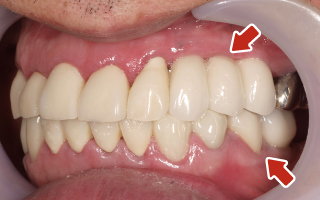

Before

After

| 55歳 男性 | |

|---|---|

| 主訴 | 前歯でしか咬めなく、食事を摂るのに非常に困難で辛い |

| 処置内容 | 上顎6本、下顎3本 |

| 治療費用 | 上顎: 約230万(税込) 下顎: 約120万(税込) |

| 治療期間 | 上顎: 1年(仮歯まで8ヶ月) 下顎: 8ヶ月(仮歯まで5ヶ月) |

| リスク | 上部構造物、仮歯の破折、術後の腫れ(3日)、人工歯根脱落リスクがあります |